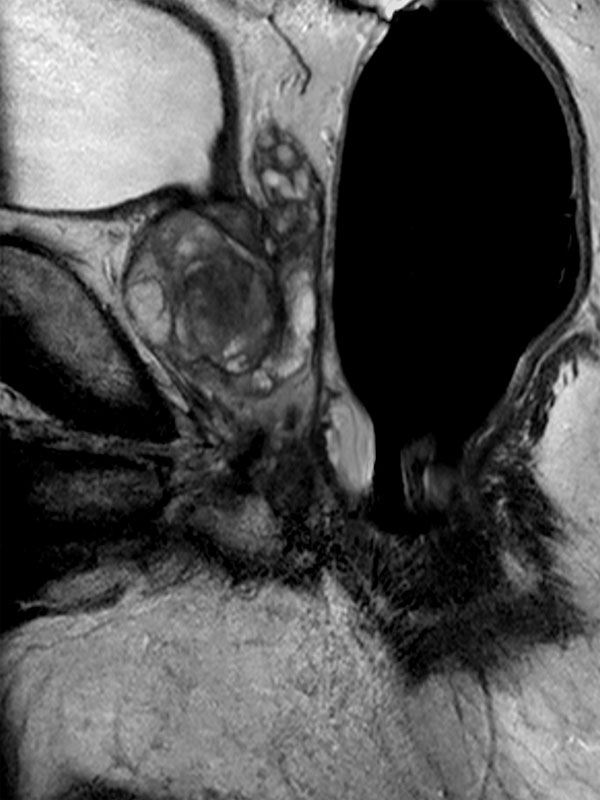

75-year old male. dS Endo coil used to visualize tumor in peripheral gland.

Sagittal T2w TSE